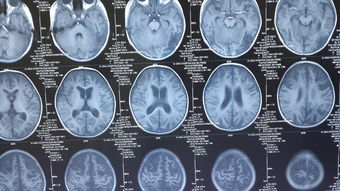

磁共振成像(MRI):是首选的检查方法,能提供多序列、多平面的高分辨率图像,福东健康网对肿瘤定位、定性及评估与周围重要结构的关系至关重要^。

平扫:室管膜瘤在T1加权像上常呈等或稍低信号,T2加权像上呈高信号。肿瘤常表现为边界相对清楚的分叶状肿块,内部信号常不均匀,反映其囊变、坏死、钙化或出血等成分^。

增强扫描:肿瘤实性部分通常呈现不均匀的明显强化,强化模式可为斑片状、结节状或环状^。典型的“铸型生长”模式在MRI矢状位和轴位图像上显示得尤为清晰,可见肿瘤填充第四脑室并可能经正中孔向下延伸^。

脑脊液电影成像:可用于动态评估脑脊液流动情况,直观显示在第四脑室出口等关键部位的梗阻^。

通过影像学,医生不仅能明确第四脑室占位的性质和范围,还能精确判断梗阻性脑积水的程度、脑室扩张的模式以及是否存在脑疝等紧急情况,为制定治疗方案提供决定性依据^。